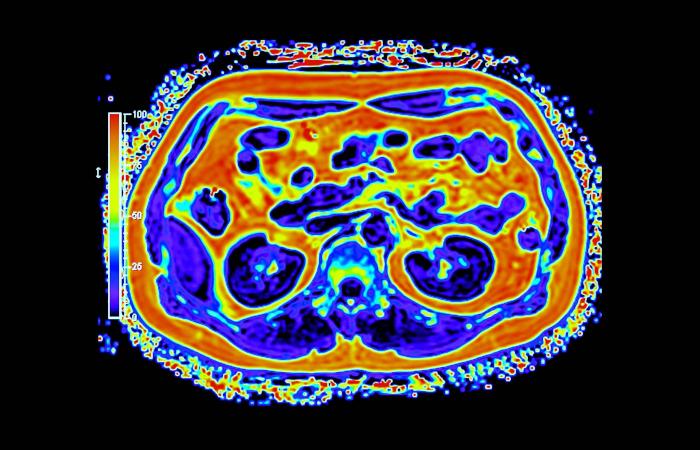

غالباً ما يُتناول تحوّل القطاع الصحي عبر محطات واضحة للعيان، مثل إنشاء مستشفيات جديدة، وإطلاق منصات رقمية، واعتماد أجهزة طبية متقدمة. غير أنّ جانباً أقل ظهوراً وأكثر حسماً يتمثل في بناء بنية تحتية تشخيصية قادرة على دعم الاكتشاف المبكر والطب الدقيق والرعاية الوقائية على نطاق وطني. ويقع التصوير الجزيئي، ولا سيما التقنيات الهجينة، مثل «PET - MRI» في صميم هذا التحول.

وعلى خلاف التصوير التقليدي، يجمع التصوير الجزيئي بين التفاصيل التشريحية والبيانات الوظيفية الآنية، ما يتيح للأطباء رؤية كيفية عمل الأنسجة لا مجرد شكلها. وفي مجالَي الأورام والأمراض العصبية، قد يُحدث هذا الفرق تحولاً في توقيت الاكتشاف أو في تعديل خطط العلاج أو في تجنّب إجراءات غير ضرورية. غير أن توسيع هذه القدرات عبر بلد واسع ومتنوّع جغرافياً يطرح تحديات تتجاوز كثيراً مجرد اقتناء الأجهزة.

أحرزت السعودية تقدماً تدريجياً في نشر أنظمة التصوير المتقدم، بما في ذلك «PET - CT» و«PET - MRI» داخل مراكز طبية كبرى. وبحسب الدكتور سامح الشيخ المدير العام لشركة التصوير الجزيئي والقطاع الطبي بوادي جدة، أثبتت هذه التقنيات قيمتها السريرية عبر الكشف عن انتشار سرطاني أو اضطرابات لم تُظهرها وسائل التصوير التقليدية، ما أتاح تعديل العلاج فوراً في عدد من الحالات.